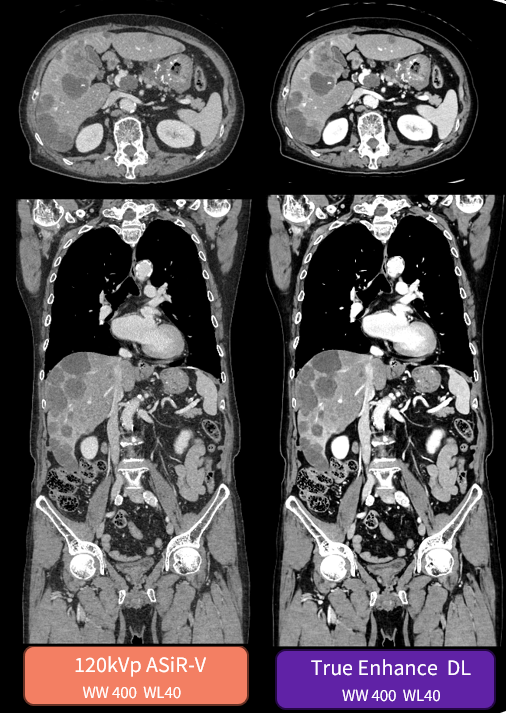

True Enhance DL (CT) – recently FDA cleared – generates deep learning-based images that can estimate monochromatic 50keV images from single-energy X-ray, to increase contrast and support confident diagnoses. The AI-based solution provides clinicians a simple workflow and incredible image quality. True Enhance DL is now available to new and existing Smart Subscription customers.

“The sharpness of the images is a breakthrough development in image reconstruction algorithms. We see details that we have never seen before. Abdominal, lung and cardiac imaging benefits most from this technology. I am mainly interested in cardiac and cardiovascular imaging. We found much better image quality, depiction of details, and image sharpness for cardiac valves, sclerotic and soft plaque in cardiac and extracardiac vessels, as well as fewer artifacts around stents and stent-grafts. DECT for pulmonary embolism easily convinced everybody in our department.” — Prof. Klaus Hergan, University Hospital Salzburg, Austria Department of Radiology of the 1200-bed University Hospital Salzburg[xi]

[ix] Image quality comparisons between DLIR and ASiR-V, were evaluated by phantom tests of MTF, SSP, axial NPS, standard deviation of image noise, CT Number accuracy, CNR, and artefact analysis. Additionally, LCD was demonstrated in phantom testing using a model observer with the head and body MITA CT IQ Phantoms (CT191, CT189 The Phantom Laboratory). DLIR and ASiR‐V reconstructions were performed using the same raw data.

[x] As demonstrated in a clinical evaluation consisting of 60 cases and 9 physicians, where each case was reconstructed with both DLIR and ASiR‐V and evaluated by 3 of the physicians. In 100% of the reads, DLIR’s image sharpness was rated the same as or better than ASiR‐V’s. In 91% of the reads, DLIR’s noise texture was rated better than ASiR‐V’s. This rating was based on each individual reader’s preference.